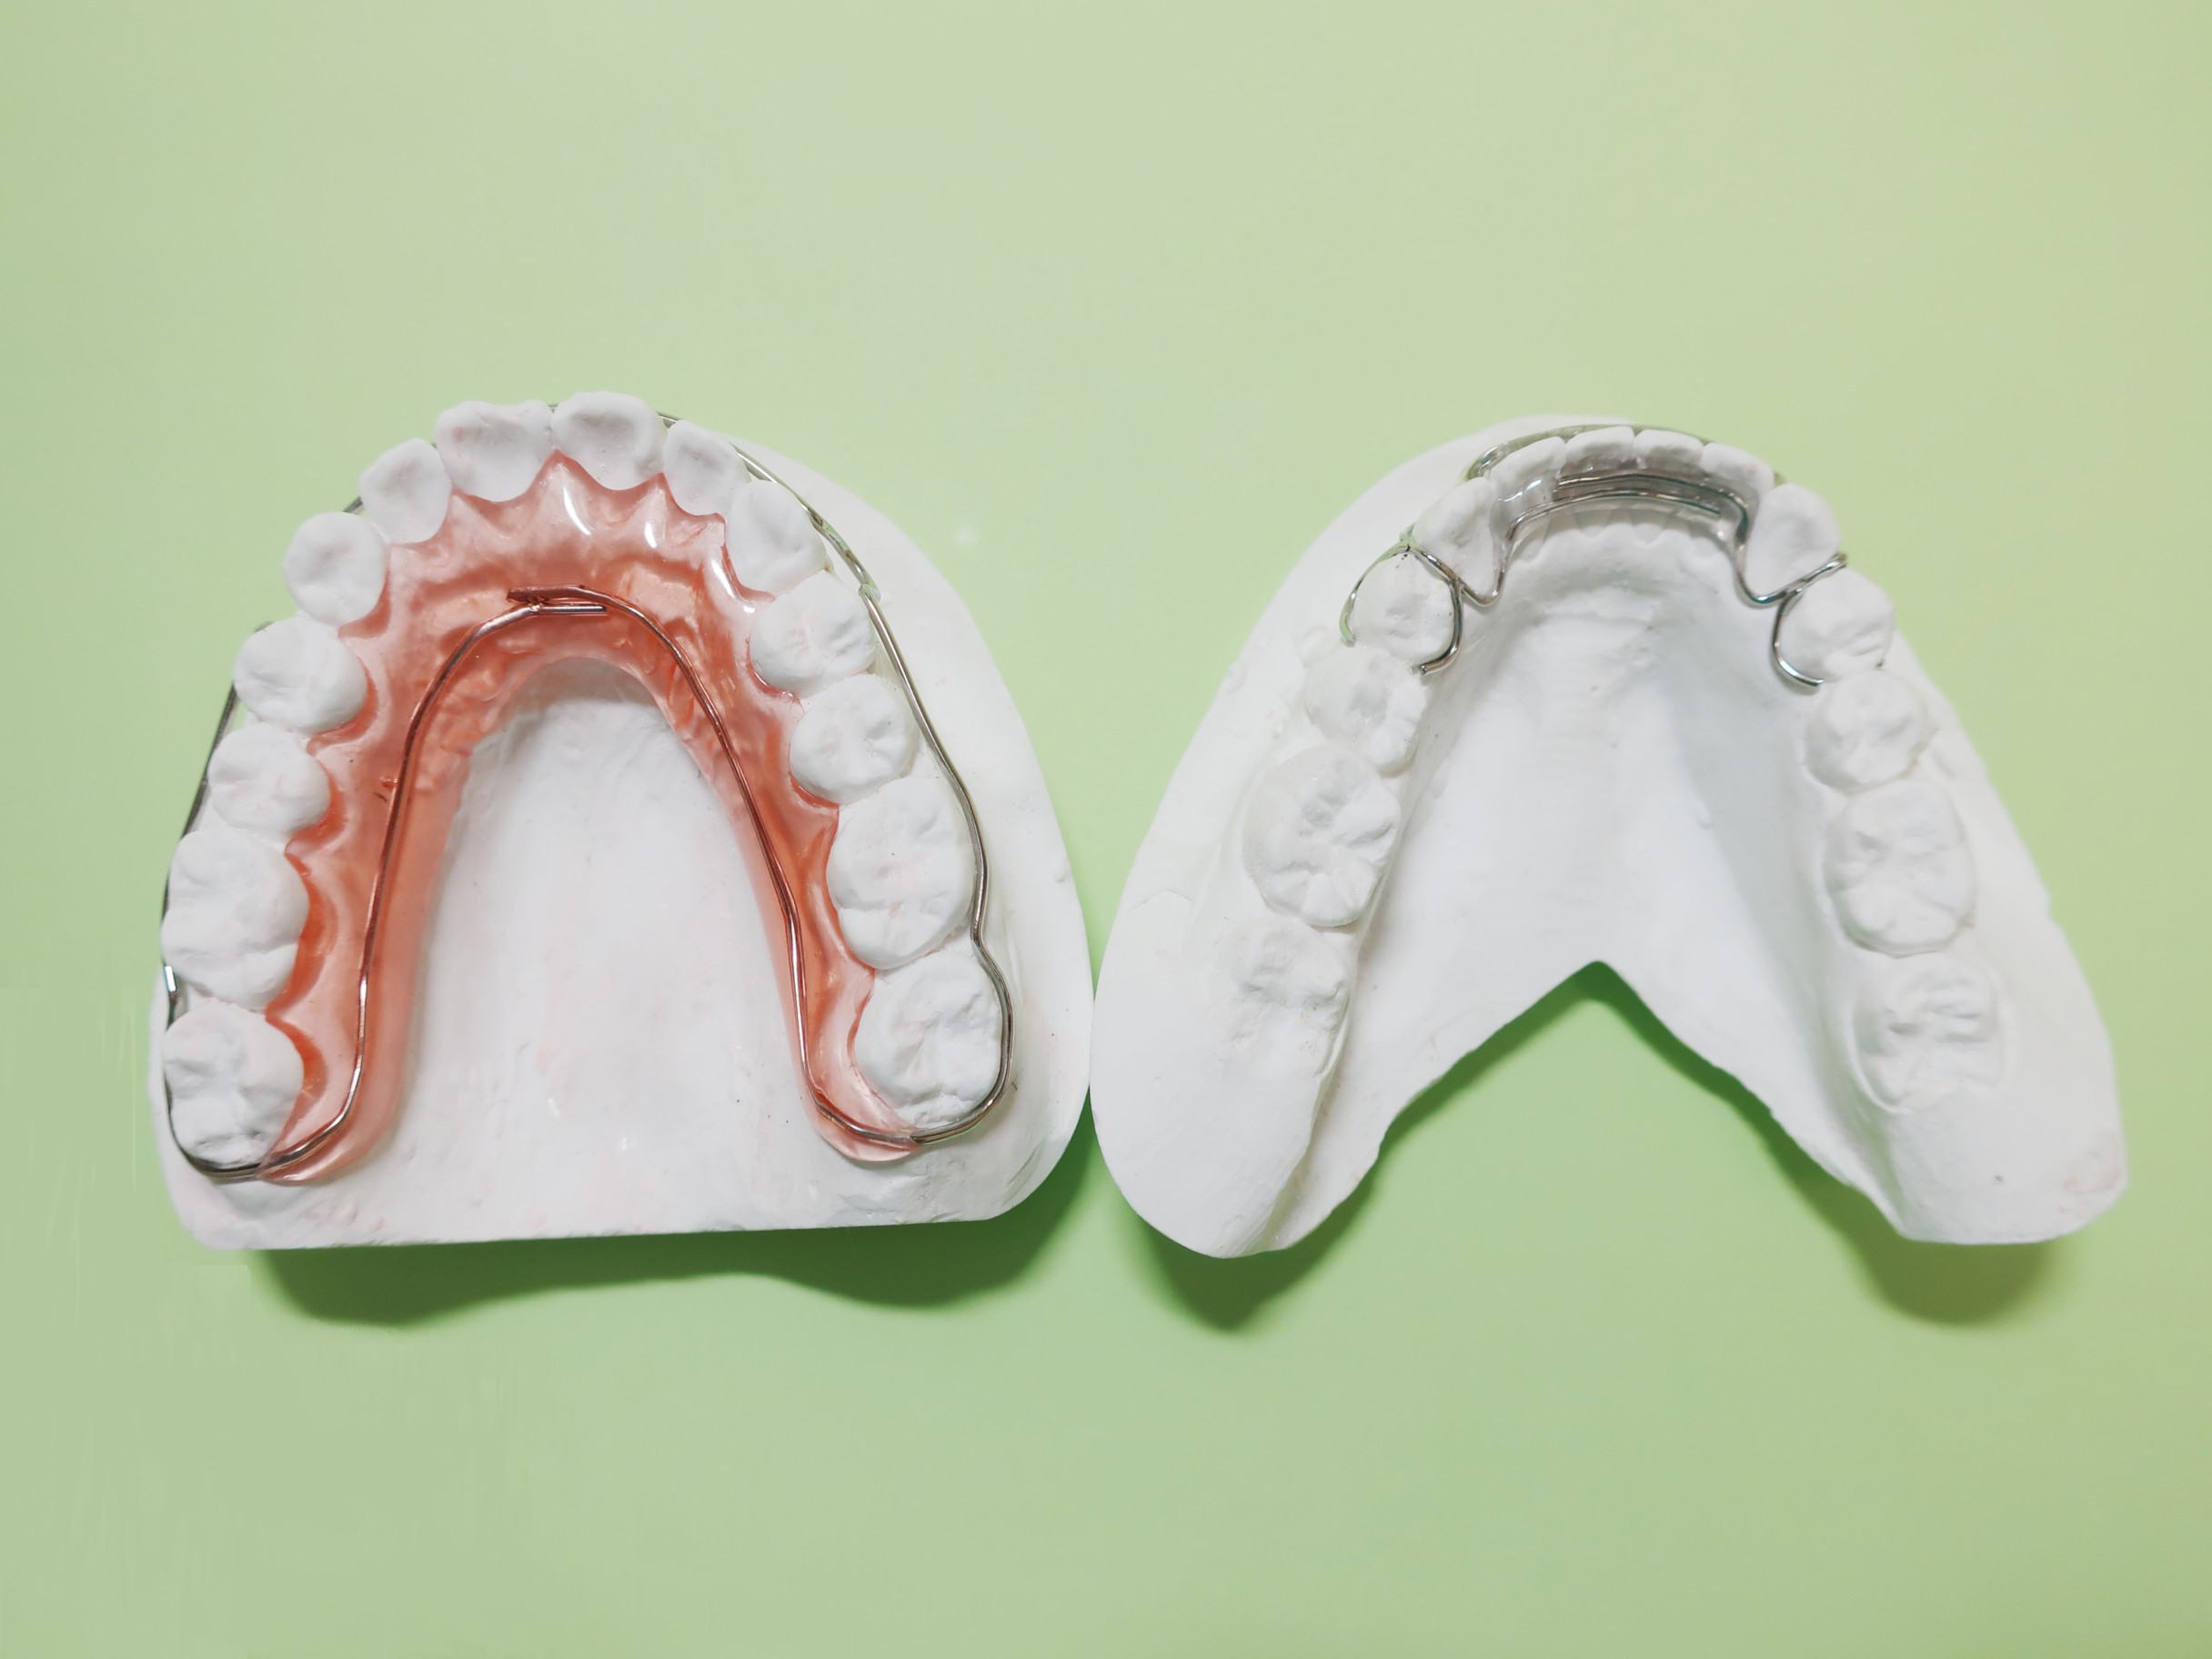

(主な治療装置)リンガルアーチ

(抜歯部位)非抜歯

(治療期間)5カ月

(治療費)¥290000

(個別リスク・副作用)上顎前歯部を前方(唇側)に傾斜させるため、下顎の前歯部からの突き上げがあり、歯根が吸収するリスクがあります。

思春期性成長のためにまた反対咬合になる可能性があります。そのため長期にわたり成長を観察する必要があります